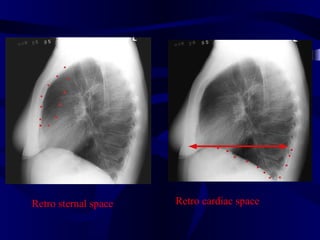

Retro sternal space Retro cardiac space